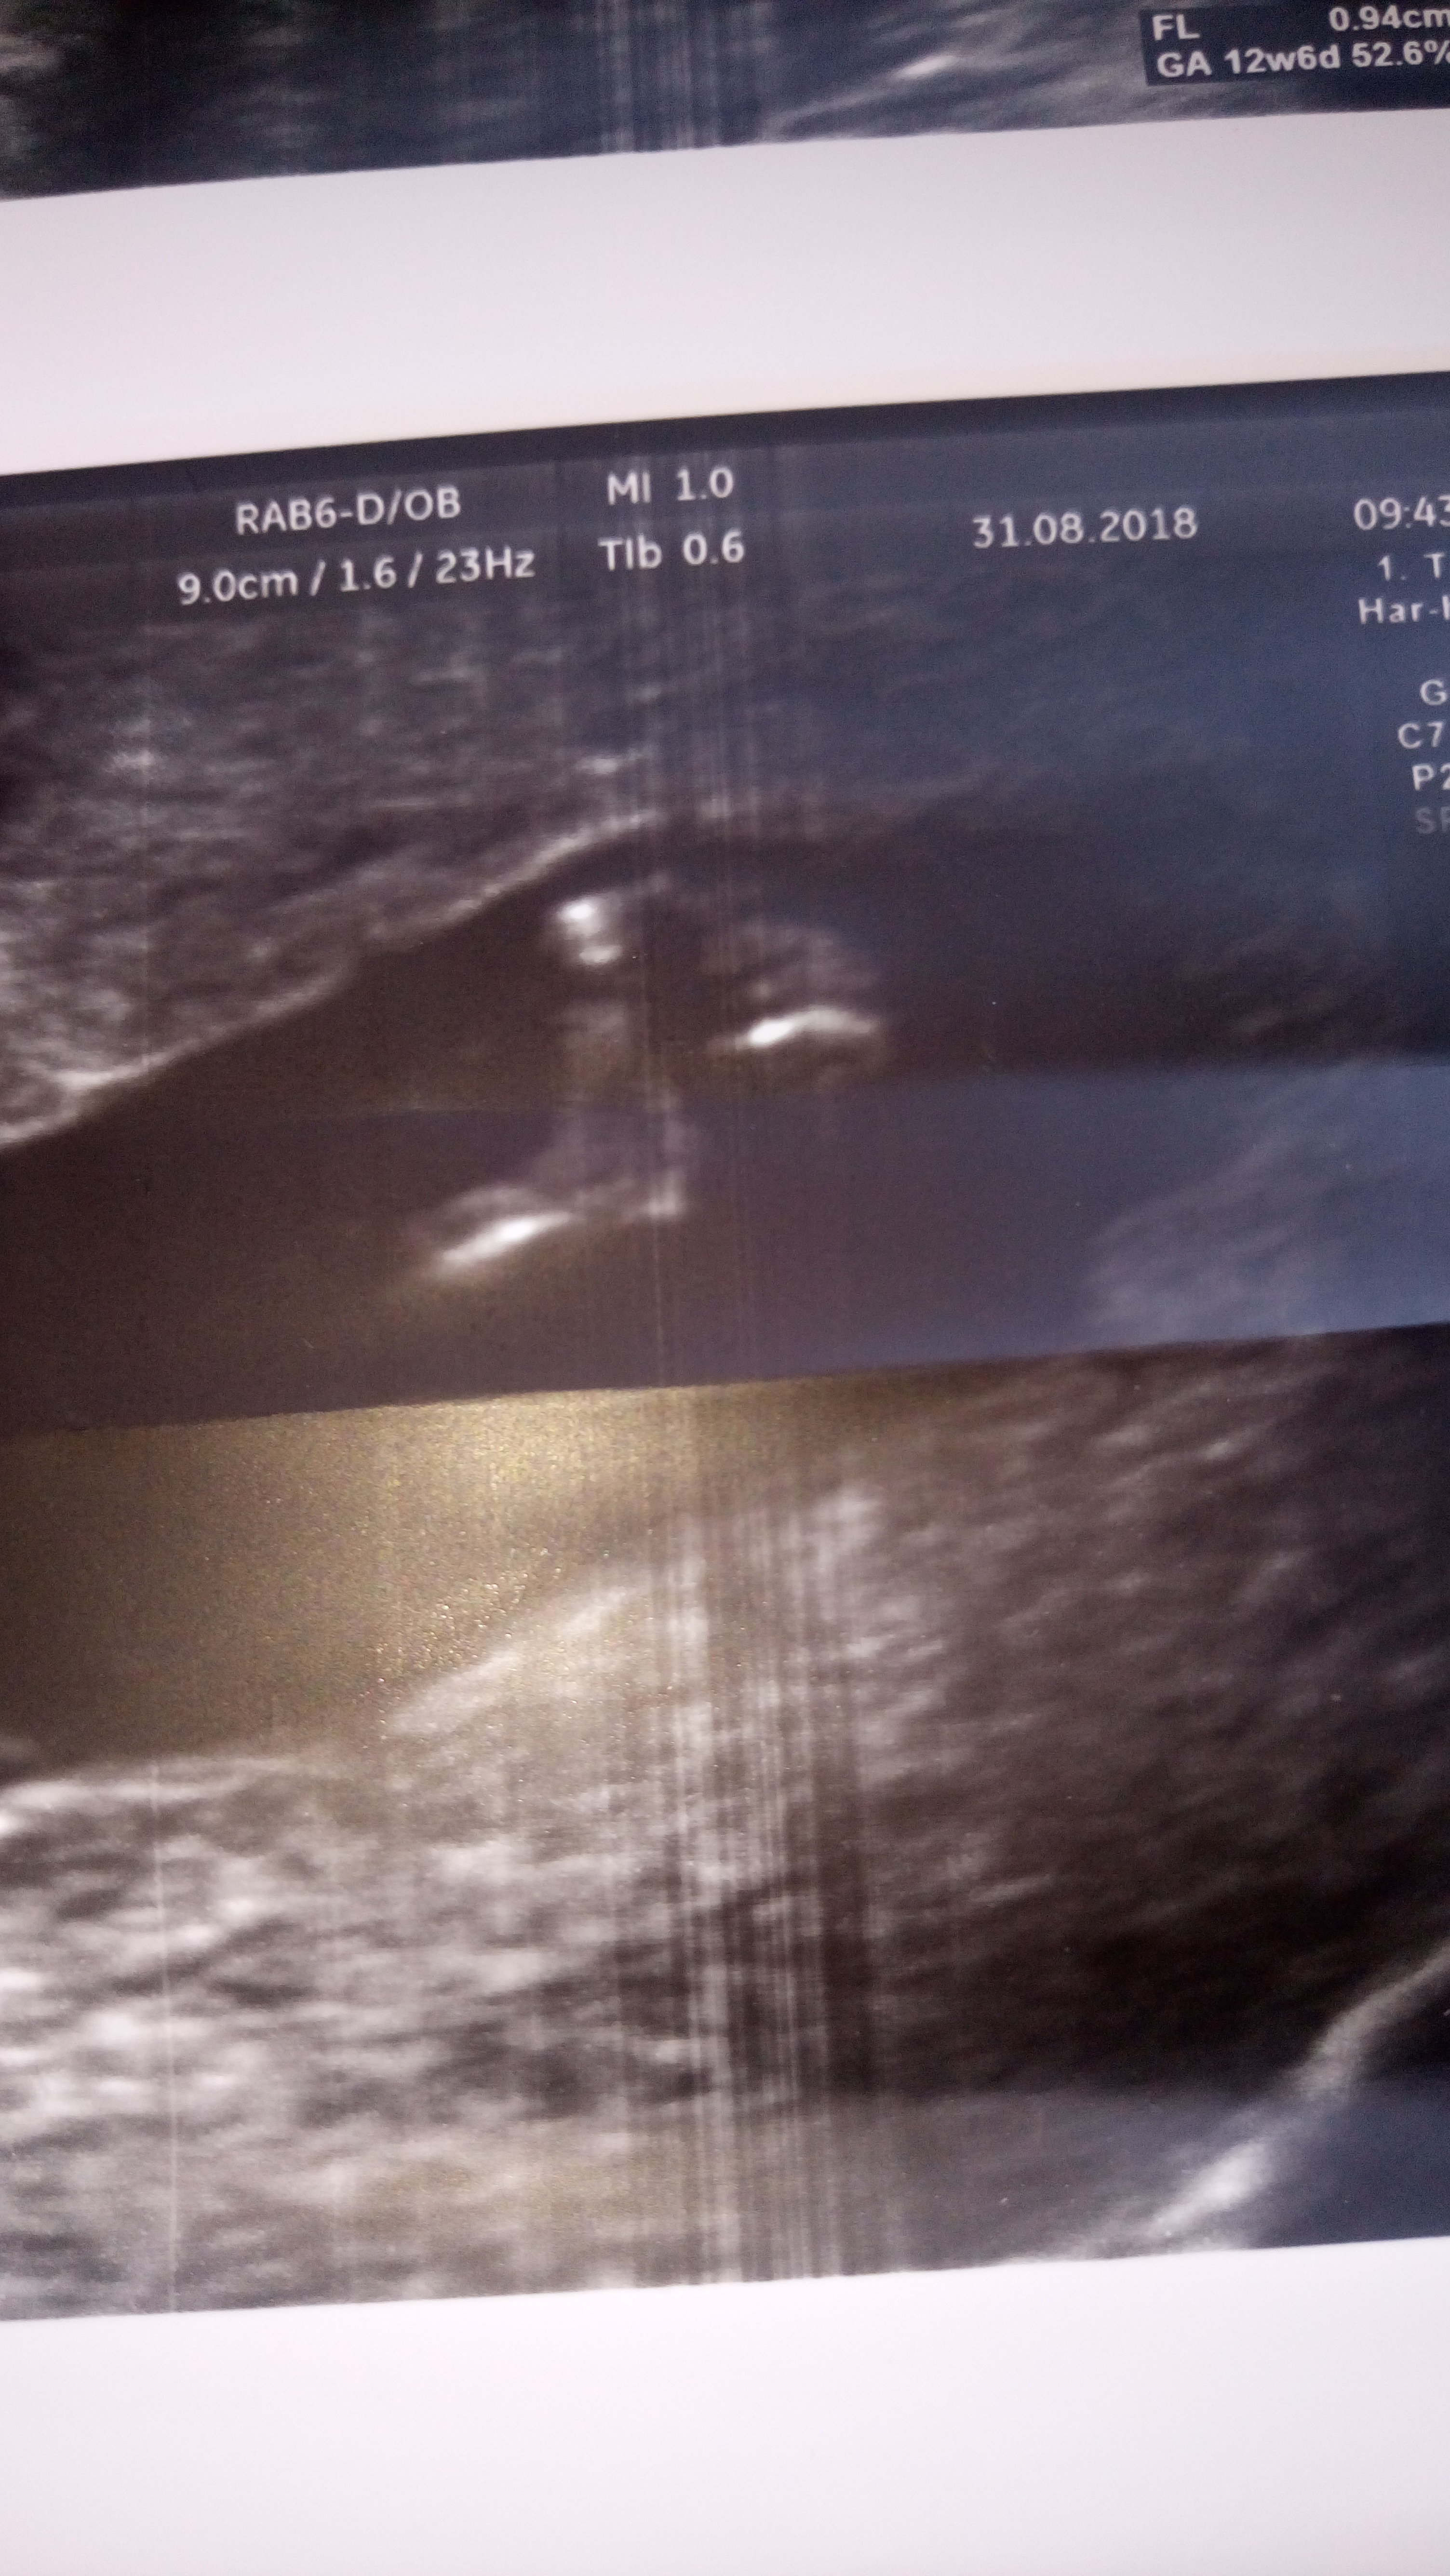

Witam Was. Może po tych zdjęciach da się odczytać płeć dzidziusia? Dodam że jest to 12+4 tc na prenatalnych Pani dr nie była pewna zajrzała tylko między nóżki na wyrostek nie patrzyła.

• DSC_2505.JPG